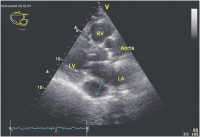

Echokardiographie aktuell: Tubuläre Struktur im Bereich des Sulcus atrioventricularis links bei 2 Patienten

Journal für Kardiologie - Austrian Journal of Cardiology 2009; 16 (1-2): 46-47 Volltext (PDF) Abbildungen mit Filmsequenzen